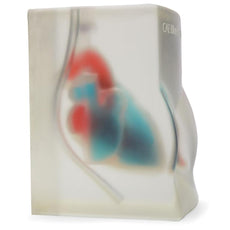

Gain proficiency in performing transvaginal ultrasound exams with our CAE Blue Phantom female pelvis models. The patented Simulex internal tissue allows learners to develop, practice and verify ultrasound imaging skills, including using ultrasound system controls, positioning and moving the transducer, recognizing internal pelvic anatomy and pathology and using gynecological ultrasound calculation packages to measure cysts, masses, and other structures. These models are excellent for 2D, 3D, and 4D ultrasonography imaging techniques. Choose from three options: General Pathology, Intrauterine & Ectopic Pregnancy, or Sonohysterographay & Sonosalpingography.